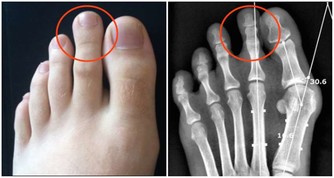

所以有一些骨質疏鬆的病人,或是更年期的婦女,當鈣質需要量增加時,專家就會建議含有草酸的蔬菜要跟牛奶分開食用,但偶爾為之造成的風險其實是不大的。